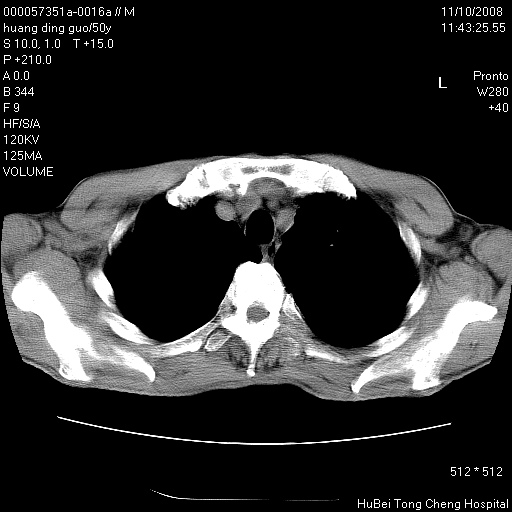

患者 男,50岁。左侧腰背部疼痛3月余,伴消瘦。平素健康,无传染病史。

胸部ct轴位平扫(层厚10mm,螺距1.5,重建间隔10mm),图像如下:

左肺下叶背段有一厚壁空洞,外壁呈锯齿状伴毛刺改变。空洞相邻胸膜有牵拉改变。左肺下叶血管支气管束不规则增粗,小叶间隔增厚。胸椎骨质破坏。考虑左肺下叶周围型肺癌伴左肺下叶癌性淋巴管炎、胸椎转移。

左肺下叶背段有一厚壁空洞,外壁呈锯齿状伴毛刺改变。空洞相邻胸膜有牵拉改变。左肺下叶血管支气管束不规则增粗,小叶间隔增厚。胸椎骨质破坏。考虑左肺下叶周围型肺癌伴阻塞性肺炎、胸椎转移。其他待排

左肺下叶背段有一厚壁空洞,内壁不规则,外壁呈锯齿状伴毛刺改变。空洞相邻胸膜有牵拉改变。周围呈絮状炎性改变,左肺下叶血管支气管束不规则增粗,小叶间隔增厚。胸椎骨质破坏。考虑左肺下叶周围型肺癌伴左肺下叶阻塞性肺炎、胸椎转移。